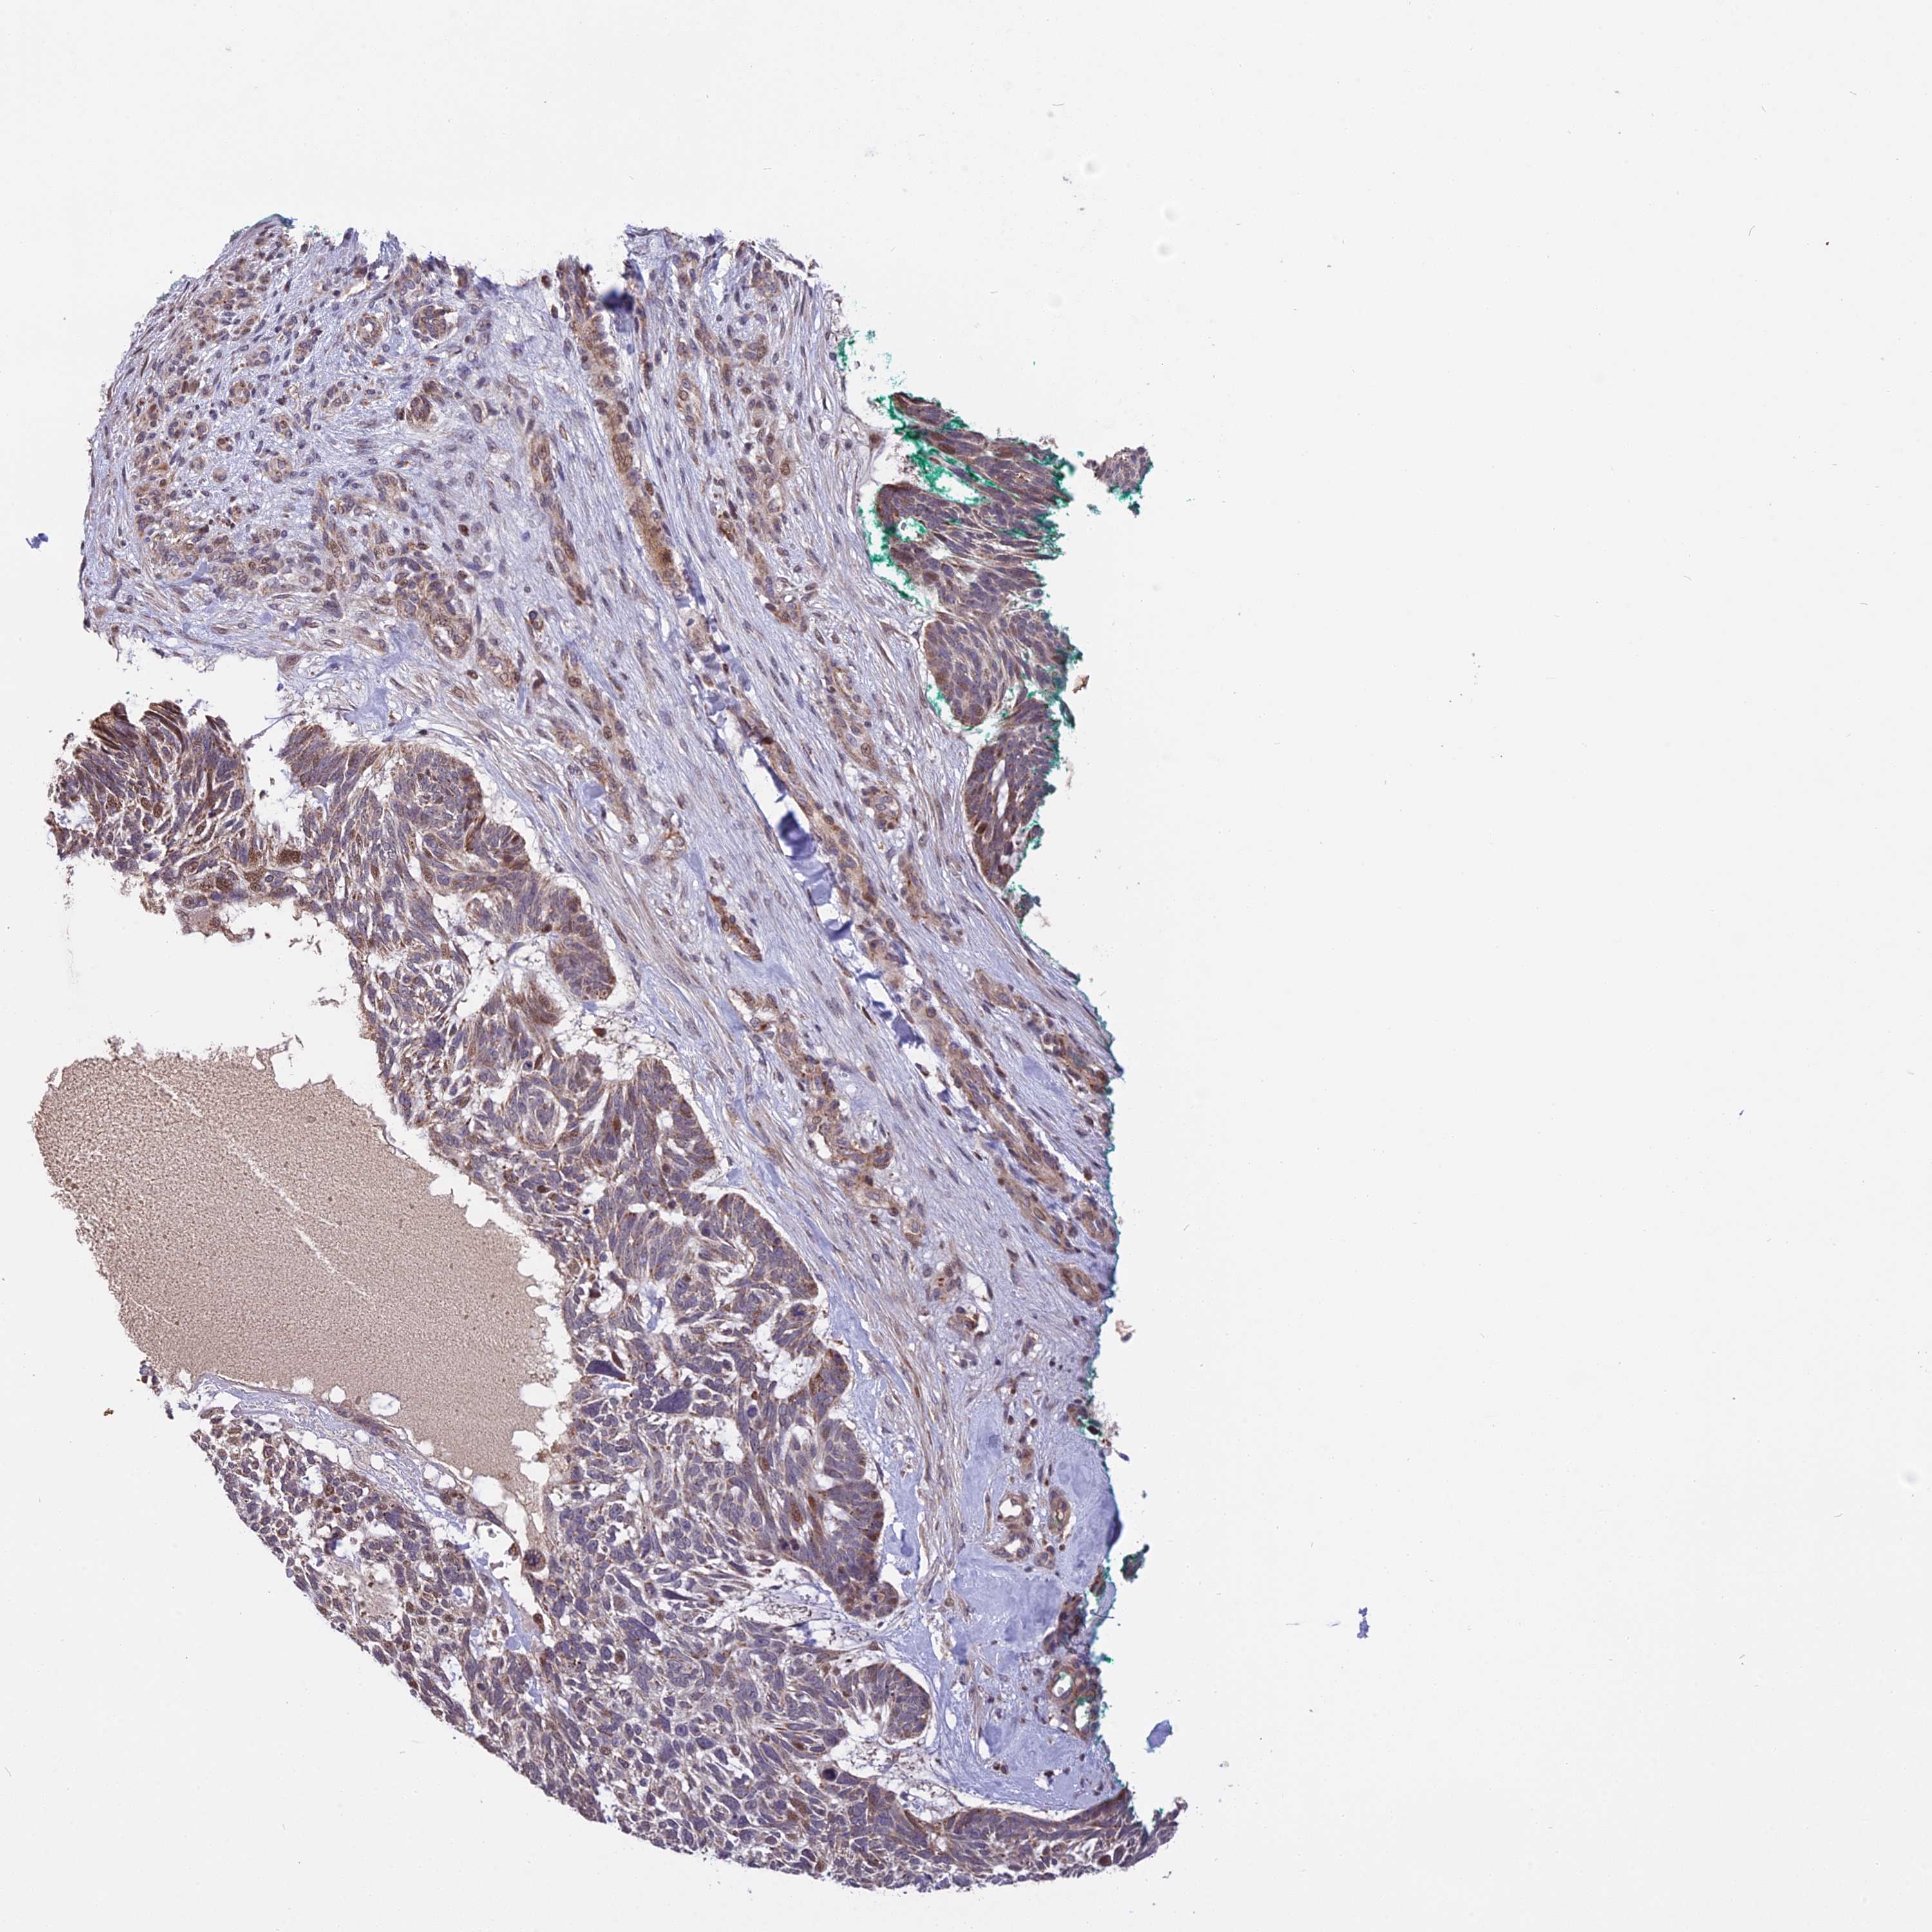

SKIN CANCER - Protein expressioni

A mouse-over function shows sample information and annotation data. Click on an image to view it in a full screen mode. Samples can be filtered based on level of antibody staining by selecting one or several of the following categories: high, medium, low and not detected. The assay and annotation is described here.

Antibody stainingi

Antibody staining in the annotated cell types in the current human tissue is reported as not detected, low, medium, or high, based on conventional immunohistochemistry profiling in selected tissues. This score is based on the combination of the staining intensity and fraction of stained cells.

Each image is clickable and will lead to virtual microscopy that enables deeper exploration of all samples and also displays staining intensity scores, fraction scores and subcellular localization as well as patient and tissue information for each sample.

Antibody HPA041740

Staining

High

Medium

Low

Not detected

Intensity

Strong

Moderate

Weak

Negative

Quantity

>75%

75%-25%

<25%

None

Location

Nuclear

Cytoplasmic/membranous

Cytoplasmic/membranous,nuclear

Basal cell carcinoma